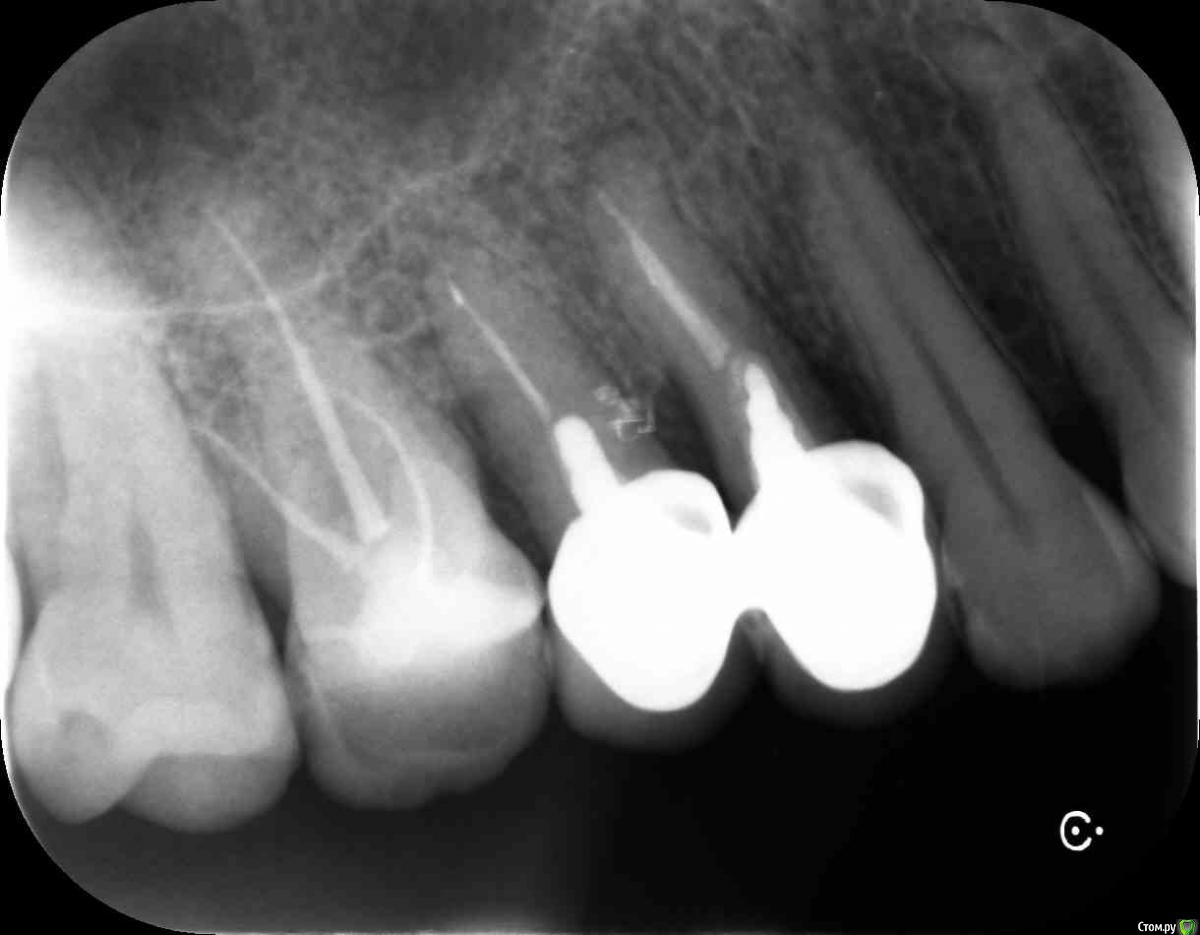

Анжела 66 Опубликовано 8 апреля, 2016 Поделиться Опубликовано 8 апреля, 2016 Добрый день, уважаемые доктора. Хотелось бы узнать ваше мнение о шансах верхней 4-ки и 5-ки.Первый, панорамный снимок, был сделан за день до появления флюса над верхней 4-кой .Второй, прицельный снимок, был сделан уже через пару дней после вскрытия флюса и наложения антибактериальной мази.Из-за небольшой подвижности резекцию корня не делали. Так же удаление штифтов не планируют. Был проведен только закрытый кюретаж, многократное наложение антибактериальной мази и длительное ( более месяца) полоскание Хлоргексамедом. Затем еще профессиональная чистка зубов.В настоящий момент оба зуба пока в спокойном состоянии. Но надолго ли? Что можно было бы предпринять еще?Заранее благодарю за ваши ответы Ссылка на комментарий

Ker Опубликовано 9 апреля, 2016 Поделиться Опубликовано 9 апреля, 2016 Добрый день, уважаемые доктора. В настоящий момент оба зуба пока в спокойном состоянии. Но надолго ли? Что можно было бы предпринять еще? Здравствуйте, увы, ненадолго. В канале(ах) четвертого зуба ложный ход и перфорация. Плюс уже приличная убыль костной ткани. Перелечить вряд-ли возможно (и особого смысла не имеет), удаление и имплантация, имхо. Ссылка на комментарий

St. Опубликовано 9 апреля, 2016 Поделиться Опубликовано 9 апреля, 2016 В случае удаление, оба зуба идут на удаление? Нет никакой возможности какой нибудь из двух зубов спасти?4 на удаление, 5 - шансы есть, если там тоже нет перфорации от штифта. Ссылка на комментарий